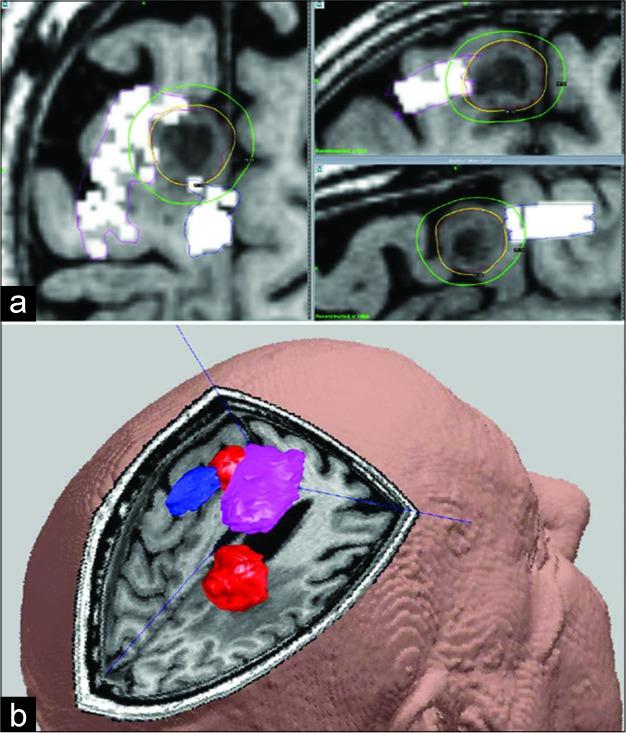

The first case was a 53-year-old female patient with metastatic breast cancer who developed focal epileptic seizures and weakness of the left hand. The magnetic resonance imaging (MRI) scan demonstrated a 30 mm metastasis neighboring the right precentral gyrus and central sulcus. The lesion was treated with adaptive hypofractionated GKRS following preoperative nTMS-based motor mapping. Subsequent follow-up imaging (up to 12 months) revealed next to complete tumor ablation without toxicity. The second case involved a previously healthy 73-year-old male who similarly developed new left-handed weakness. A subsequent MRI demonstrated a 26 mm metastatic lesion, located in the right postcentral gyrus and 5 mm from the hand motor area. The extracranial screening revealed a likely primary lung adenocarcinoma. The patient underwent preoperative nTMS motor mapping prior to treatment. Perilesional edema was noted 6 months postradiosurgery; nevertheless, long- term tumor control was demonstrated. Both patients experienced motor function normalization shortly after treatment, continuing to final follow-up.

第一例是一名53岁的转移性乳腺癌女性患者,出现局灶性癫痫发作和左手无力。磁共振成像(MRI)扫描显示在右侧中央前回和中央沟附近有一个30毫米的转移瘤。在基于术前nTMS的运动功能区定位后,该病变接受了适应性低分割GKRS治疗。随后的随访成像(长达12个月)显示肿瘤几乎完全消融且无毒性。第二例是一名73岁的既往健康男性,同样出现了新的左手无力症状。随后的MRI显示一个26毫米的转移瘤,位于右侧中央后回,距手部运动区5毫米。颅外筛查显示可能为原发性肺腺癌。该患者在治疗前接受了术前nTMS运动功能区定位。放射外科治疗后6个月发现瘤周水肿;尽管如此,仍显示出长期的肿瘤控制效果。两名患者在治疗后不久运动功能均恢复正常,并持续至最终随访。